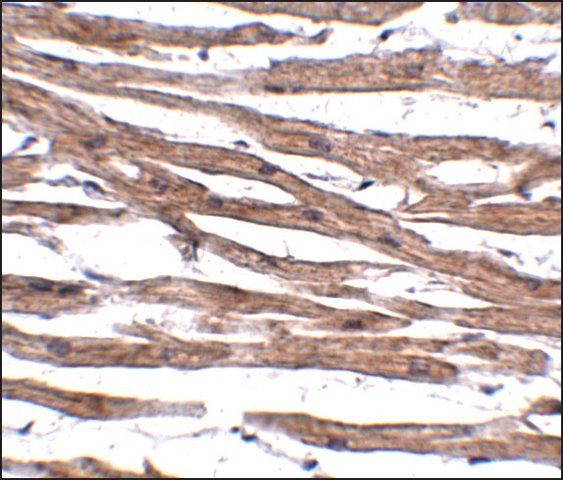

MAGEA6 is a member of the MAGEA gene family. The members of this family have their entire coding sequences located in the last exon, and the encoded proteins show 50 to 80% sequence identity between each other. The promoters and first exons of the MAGEA genes show considerable variability, suggesting that the existence of this gene family enables the same function to be expressed under different transcriptional controls. The MAGEA genes are expressed at a high level in a number of tumors of various histologic types, and are silent in normal tissues with the exception of testis and placenta. The MAGEA genes are clustered on chromosome Xq28. They may be implicated in some hereditary disorders, such as dyskeratosis congenita.

This antibody is generated from rabbits immunized with a KLH conjugated synthetic peptide selected from the C-terminal region of human MAGEA6.